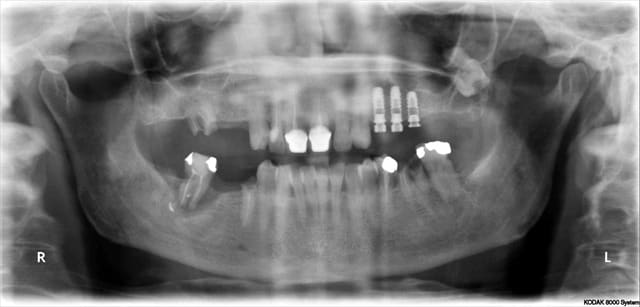

27/02/2014 à 11h55

Jeamba progresse doucement mais surement!

j'utilise un de ces cas pour répondre à chiroraledijon et acid

Je l'ai déjà dit souvent, la base ce sont les images dicom

et lorsqu'un radiologue donne cela!!!!!! évidemment le résultat sera imprécis et très chronophage

Le fichier gencive est totalement inutilisable

Jeamba confirmera que le radiologue lui a dit que scanner un plâtre cela ne donnerait rien (résultat en rouge):-)